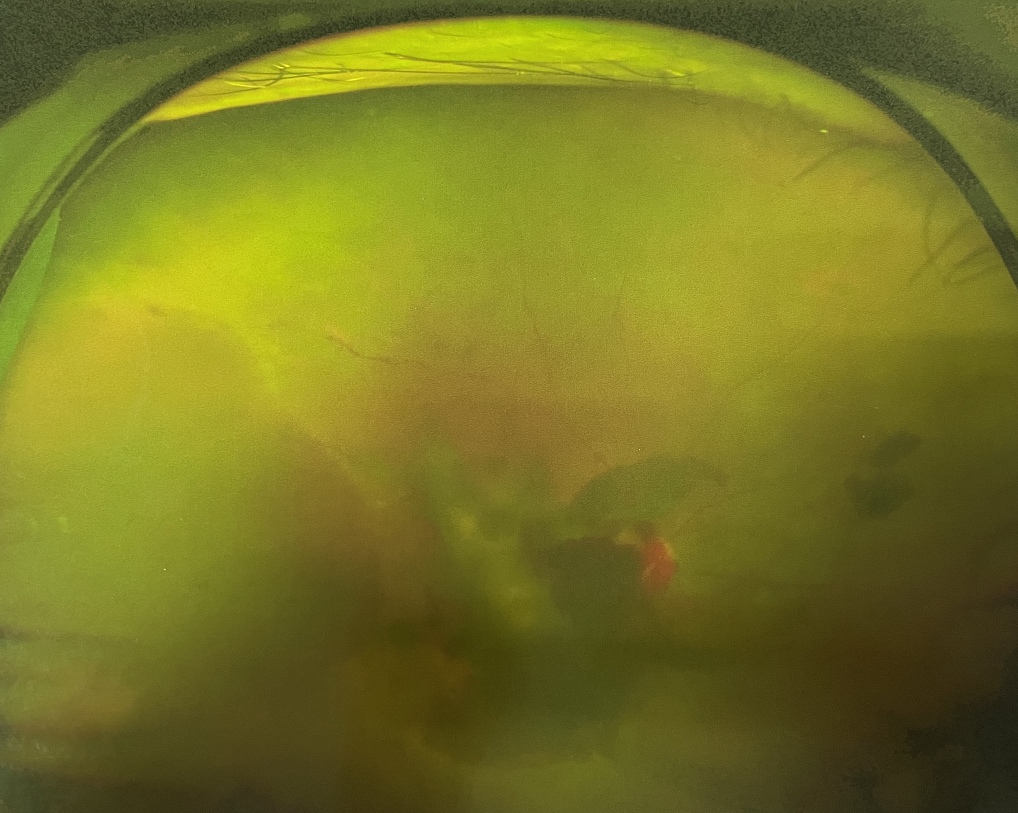

四十多歲的王女士,患高血壓病及Ⅱ型糖尿病多年,一直靠藥物控制血壓和血糖。去年,王女士右眼看手機(jī)時(shí)感覺視物不清,總感覺眼前有一層霧,視力也逐漸下降,于是來廈門大學(xué)附屬廈門眼科中心就診。

眼底病專科張小虎醫(yī)生檢查后,診斷王女士為“雙眼玻璃體積血、雙眼糖尿病視網(wǎng)膜病變V期”。(V期即5期,纖維增生期,出現(xiàn)纖維膜,可伴視網(wǎng)膜前出血或玻璃體出血。)

張小虎醫(yī)生為王女士進(jìn)行右眼玻璃體腔注藥術(shù),3天后進(jìn)行右眼23G玻璃體切割術(shù)后視力有所提升。

4個(gè)月后王女士來院取硅油,取油后視力恢復(fù)到0.6。“當(dāng)時(shí)來的時(shí)候真的只能看到模糊的影子,特別害怕覺得完了,想說眼睛估計(jì)要瞎了,沒想到手術(shù)后視力竟然提升了,現(xiàn)在也看得比較清楚了。”王女士說到。

張小虎醫(yī)生表示,糖網(wǎng)病進(jìn)展到嚴(yán)重增殖期帶來的視力損傷往往是極其嚴(yán)重的,目前王女士右眼從術(shù)前0.02恢復(fù)到術(shù)后0.6,已屬十分難得。

右眼術(shù)前